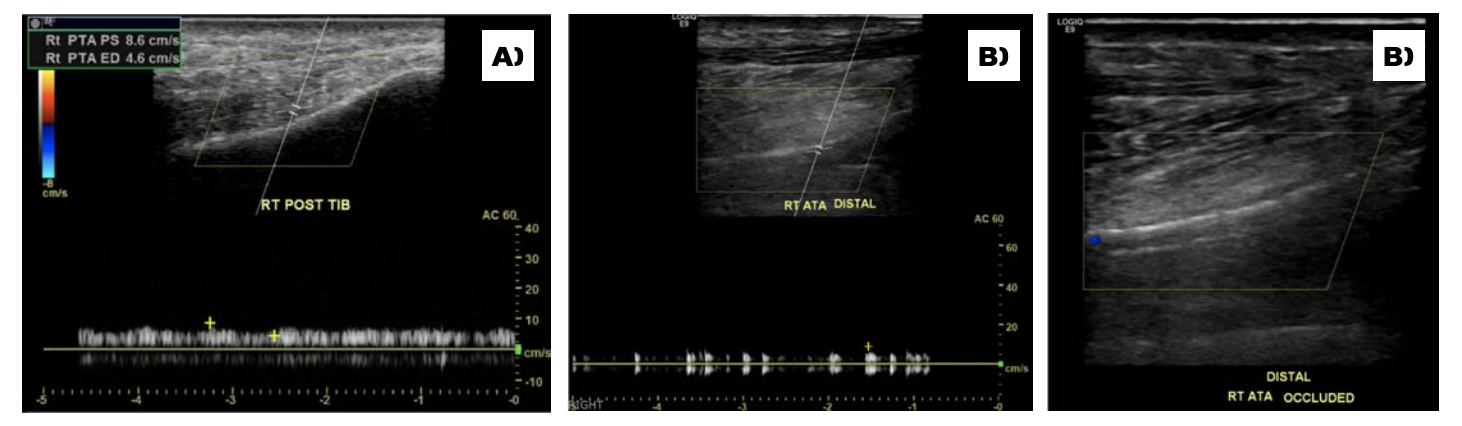

On examination, his right dorsal pedis and posterior tibialis pulses were absent. His right heel had a mature eschar on the posterior aspect with no erythema, drainage, or odor noted in addition to wounds involving his second to fifth digits. Bedside Doppler showed a diminished signal at the dorsal pedis and absent signal at the right posterior tibial. X-ray of the foot demonstrated no evidence of osteomyelitis. His vascular arterial Duplex ultrasound showed an occluded right posterior tibial DVA. The distal anterior tibial artery was severely diseased with a distal occlusion and a monophasic waveform (Figure 1A and 1B). The distal peroneal and posterior tibial arteries were occluded. The plantar veins were studied with ultrasound for possible targets for hybrid DVA using a great saphenous vein to medial marginal vein bypass; however, this was not favored after discussing with vascular surgery. He was evaluated for right below knee amputation which he refused. He was then transferred to our facility to consider other treatment options for revascularization as a last resort. He had a peripheral angiogram that showed a patent distal aorta, iliac arteries, and femoropopliteal segments. The right anterior tibial artery was diffusely diseased with a 90% critical stenosis in its distal segment (Figure 2). The right distal peroneal, posterior tibial arteries and the right posterior DVA were occluded. After careful analysis of the angiogram, we proceeded with an intervention to the anterior tibial artery to establish direct foot perfusion. The left common femoral artery was accessed under ultrasound guidance using a micropuncture needle. A 4F IMA diagnostic catheter and a 0.035 angled Glidewire were used to access the contralateral right common iliac artery. The right SFA and profunda femoral arteries were heavily calcified without severe obstructive disease. The wire was advanced into the right popliteal artery and a 5F by 90 cm Cook Flexor Shuttle was advanced to the origin of the right anterior tibial artery for good support. An Asahi Sion Black 0.014 x 300 cm guidewire was advanced and used to cross the distal anterior tibial stenosis into the dorsal pedis artery. The distal wire was advanced into the first dorsal metatarsal branch after several attempts to wire across the pedal loop. A Corsair Asahi 150 cm microcatheter was then advanced into the dorsal pedis artery and selective foot angiogram was performed. A magnified view of the right foot showed a chronic total occlusion of the dorsal pedis (Figure 3). Laser atherectomy was performed with Philips Turbo Elite 0.9 mm catheter from the origin of the anterior tibial artery to the beginning of the dorsal pedis artery at 80/80 fluency/rate (Figure 4). This was followed by balloon angioplasty with coronary balloons since other balloons will not cross at rated pressure with multiple prolonged 5-minute inflations each of the entire vessel. A Coyote 2.5 x 220 mm balloon was used to further postdilate the anterior tibial artery obtaining excellent angiographic result with improvement of the blood flow into the dorsal pedis as well as the collaterals to the posterior tibial and its plantar branches. The patient’s ischemic rest pain resolved and he was followed linearly along wound care with significant improvement few weeks later.